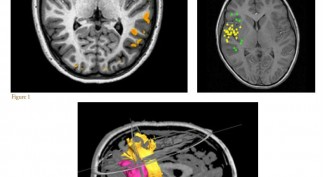

The human brain is an incredible organ about which, in comparison to other organs, relatively less is known regarding its function and networks of...